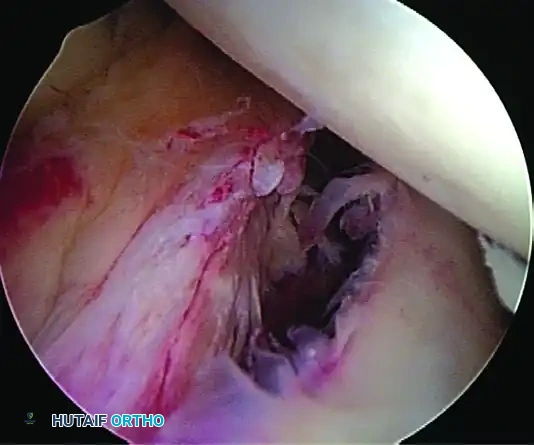

- Shuttle the PDS relay suture out the posterior cannula, load the anchor suture, and pull it through the capsulolabral tissue.

- Retrieve the corresponding suture limb and tie a secure, low-profile sliding knot (e.g., SMC or Weston knot) backed up by alternating half-hitches.

5. Recreating the Anterior Bumper

Proceed superiorly, placing the second and third double-loaded anchors. Firmly secure the sutures, compressing the capsuloligamentous complex to the abraded bone surface. This "loop and knot fixation" rolls the tissue up onto the glenoid face, recreating a robust anterior soft-tissue bumper.

D, Knots tied re-creating soft tissue bumper.

6. Rotator Interval Closure

If the patient exhibits baseline hyperlaxity and a significant sulcus sign that persists after the Bankart repair, a rotator interval closure is mandatory to address the superior glenohumeral ligament (SGHL) and coracohumeral ligament (CHL) laxity.

- Withdraw the anterior central cannula just outside the capsule.

- Pass a crescent Spectrum needle through the IGHL, several millimeters into the ligament, and into the joint.

- Maintain one limb outside the capsule. Retrieve the intra-articular limb using a penetrator device at the level of the SGHL.

- Tie the sutures extracapsularly using an SMC knot. Generally, two sutures are sufficient. The slight loss of external rotation is a necessary trade-off for the added inferior stability.

Completed Bankart repair with three anchors and capsule plicated inferiorly. Rotator interval is closed.